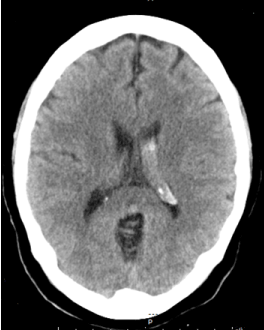

Middle-aged patient with no past medical history who was sitting in church and experienced the worse headache of his life, primarily occipital in location, prompting transfer to a nearby emergency department. Subsequent head CT (Figure 1) revealed intra-ventricular hemorrhage. Further testing with MRI/MRA (Figure 2) revealed features consistent with Moyamoya syndrome/disease. The patient was taken for angiogram, which confirmed Left MCA occlusion with left ICA ending in prominent lenticulostriate arteries consistent with Moyamoya features, and an aneurysm of the distal AChA (Figure 3). Throughout this the patient was neurologically intact and was admitted to the ICU for conservative treatment to be followed by bypass after recovery from hemorrhage. However, a repeat angiogram performed to determine any changes in aneurysm size on post-bleed day 3 revealed an increase the aneurysm size (from 3.5 to 5 mm). (Figure 4).

Figure 1. Head CT showing left intra-ventricular bleeding.